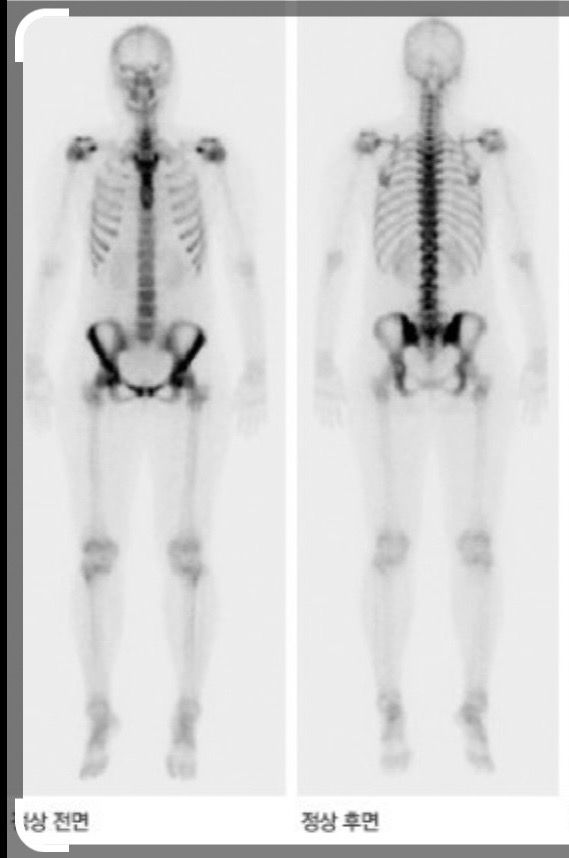

발목및 전신 뼈스캔 검사를 받았습니다 정상 소견이면 하얗게 보인다고 하는데 저는 전신에 군데군데 검은곳이 많아요…담당의(정형외과)는 다른 곳은 자기 분야가 아니어서 그런지 별말은 없었는데 저는 괜히 찜찜합니다..

**첨부한 사진은 네이버에서 정상(첫번째사진) 뼈스캔 사진으로 퍼온 사진이고 부위 설명한다고 두번째에 표시해놨습니다 (좌는 정면 우는 뒷면임)

뼈스캔 검사 결과 해석은 복잡할 수 있으며, 검은 부분이 반드시 비정상을 의미하지는 않습니다. 이는 다양한 이유로 발생할 수 있습니다. 예를 들어, 골밀도가 낮은 부위, 혈류가 적은 부위, 또는 단순히 해부학적 구조에 따른 차이일 수 있습니다. 또한, 검사 시 자세나 기술적 요인도 영향을 줄 수 있습니다. 정형외과 의사가 발목 부위에 집중했다면, 그 부분에 대해서는 정상 소견을 보였을 가능성이 높습니다. 그러나 전신 스캔 결과에 대해 궁금하다면, 핵의학과 전문의와 상담하는 것이 좋습니다. 이들은 전체적인 스캔 결과를 해석하고 추가 검사가 필요한지 판단할 수 있습니다.

뼈스캔은 민감도가 높아 골절있거나, 관절염이있을때도 양성으로 보이기도 하고, 원래 정상인 특정 뼈들도 uptake 가 된 소견이 보이기도 합니다. 평소에 기저질환이 있는지, 또는 통증이 있는지 등 임상적인 것과 연관지어서 해석을 하는 편이구요. 검사 자체만은 검사한곳에서 영상의학과가 있다면 판독을 해줄테니, 판독지를 요청해주셔서 판독을 확인해보시는게 좋겠습니다.